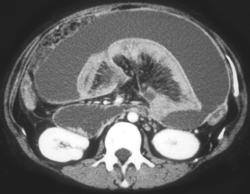

Diagnosis

Gastritis